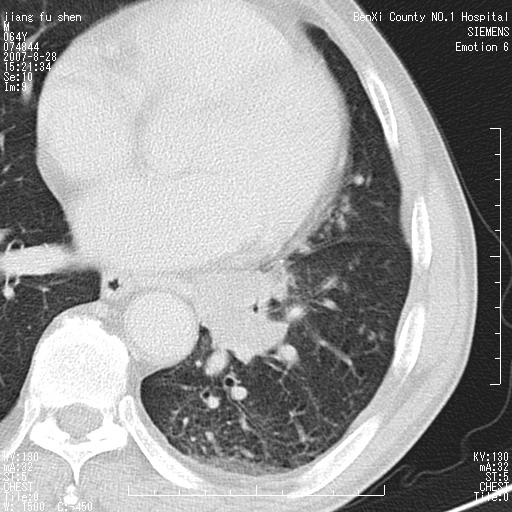

男、64、咳嗽、发烧一周、左肺呼吸音稍弱。既往肺结核,右手结核。

本次扫描患者未带原片,左肺下叶发现病灶。左肺上叶空洞,5组淋巴结肿大,1cm左右。

追问病史三月份ct扫描左肺上叶空洞,医大诊断肺结核。

平扫20-33hu

增强31-33hu

1分半44-52

2分55-67

左肺下叶前内基底段支气管明显偏心性狭窄,周围分叶状肿块,伴有阻塞性肺炎,支持肺癌可能性大。

考虑左肺中央型肺癌并阻塞性肺炎

病灶边缘可见多量较长棘影及纤维条索状影,除外病灶边缘较光整,病灶有分叶表现,但多表现为较浅分叶,且向周围伸出之叶多呈尖角改变,且边缘较光整,病灶增强呈中度延时增强,且早期及中期仅轻度增强,结合患者病史,多考虑继发型肺结核,炎性增殖灶形成,不除外肺癌

左下叶支气管变窄,管腔光滑。软组织形状不规侧,分叶呈角形。结合病史考虑结核可能性大。肺癌不除。